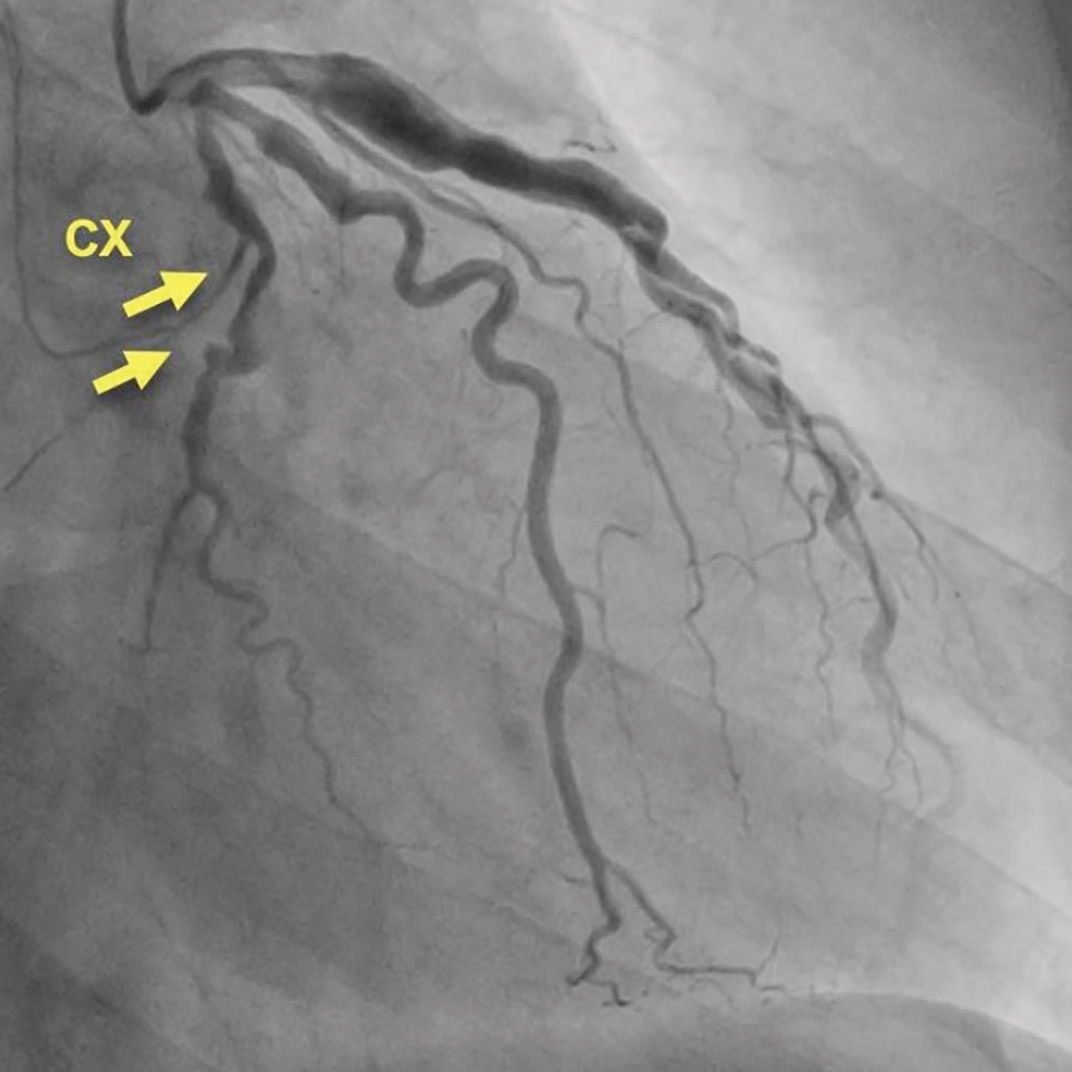

心电图和超声心动图均正常。入院时行冠脉造影检查,发现LCX近端闭塞,同时钝缘支和LAD存在扩张(图1)。术中未植入支架。

图1:病例1的初始LCX影像:完全闭塞伴扩张